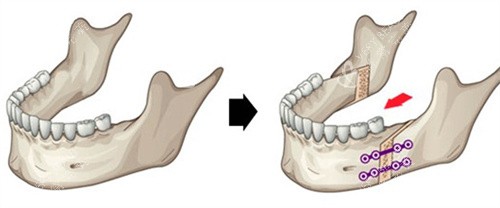

面诊那天,医生拿着我的CT片,指着骨头说:“你这是上颌前突+下颌后缩,得做双颌手术——上颌截骨后移,下颌截骨前移。”我听得云里雾里,只问了一句:“能让我侧脸不凸吗?”医生笑:“术后你的侧脸会立体很多,但得做好心理准备:前三个月肿得像猪头,半年才能正常吃饭。”我咬咬牙:“做!”

术后前三个月,我像“养伤正规户”——每天喝粥、吃蒸蛋,连苹果都得打成泥。第四个月开始,能嚼软饭了,但硬的东西还是不敢碰。第六个月复查时,医生拿着我的对比照说:“侧脸变化非常大,上颌收了5毫米,下颌前移了3毫米,现在比例很协调。”